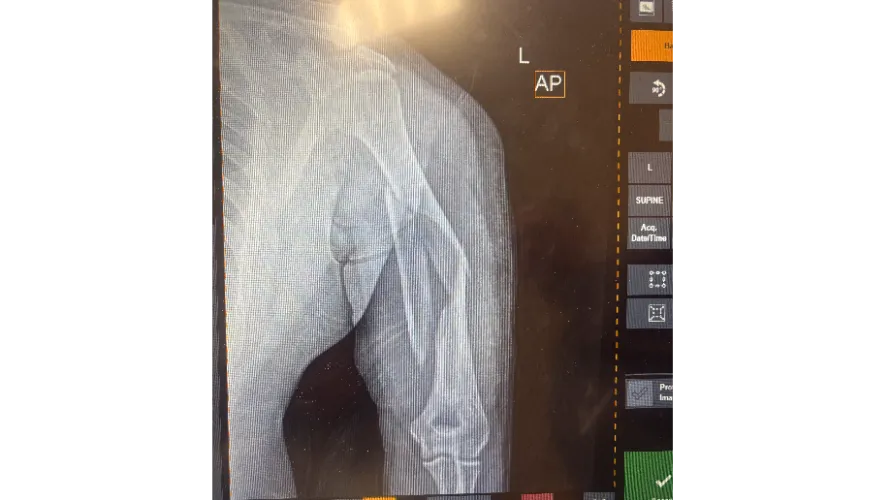

Diego was rushed by ambulance to the hospital, where he spent four long days fighting through pain and shock. Doctors discovered that his left upper arm was shattered in three places, requiring a six-hour surgery and ten screws to put it back together. He also suffered two fractures in his right foot, nerve damage that causes numbness from his lower back to behind his knee, painful road rash, bruising, and ongoing back pain. Every single day since the accident has been both a physical and emotional battle.